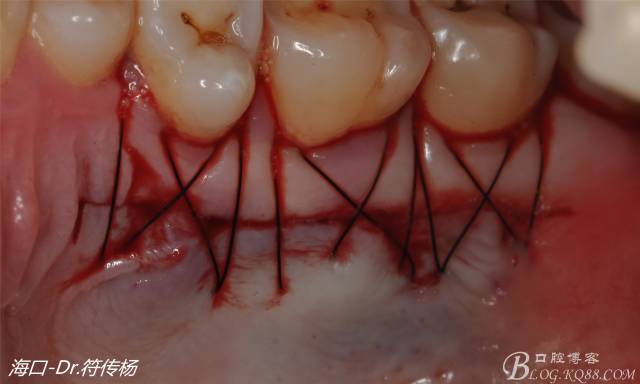

受植區(qū)建議使用雙交叉垂直懸吊縫合術(shù)來固定結(jié)締組織并能讓齦瓣更貼合根面利于術(shù)后一期愈合